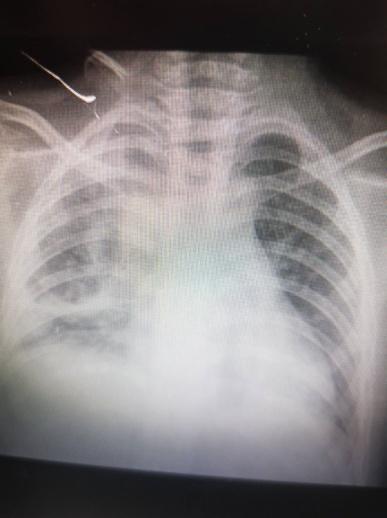

Επιπλεγμένη πνευμονιοκοκκική πνευμονία από ορότυπο 3 σε εμβολιασμένο ανοσοεπαρκή παιδιατρικό ασθενή.

Μαργαρίτα-Ευθαλία Παπασάββα, Δήμητρα Σαββίδου, Τζωρτζίνα Τζανακάκη, Ανδρέας Ηλιάδης, Βασιλική Γκέτση

Serotype 3 complicated pneumococcal pneumonia in a vaccinated immunocompetent paediatric patient.

Margarita-Efthalia Papasavva, Dimitra Savvidou, Georgina Tzanakaki, Andreas Iliadis, Vasiliki Gketsi